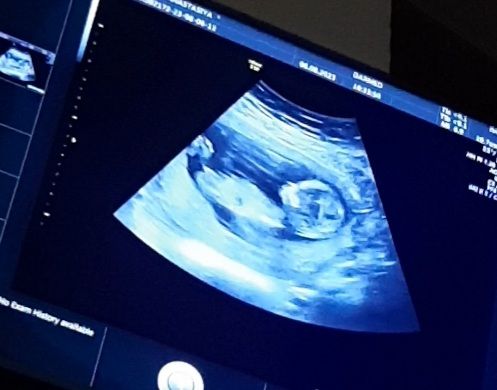

Результаты скрининга на 12-13 неделе: 80% вероятность девочки. Нужна помощь в сравнении снимков!

Изображение Нужно верить, что девочка и вселенная вас услышит). П.с. если конечно девочку хотите. Анастасия Штауб,